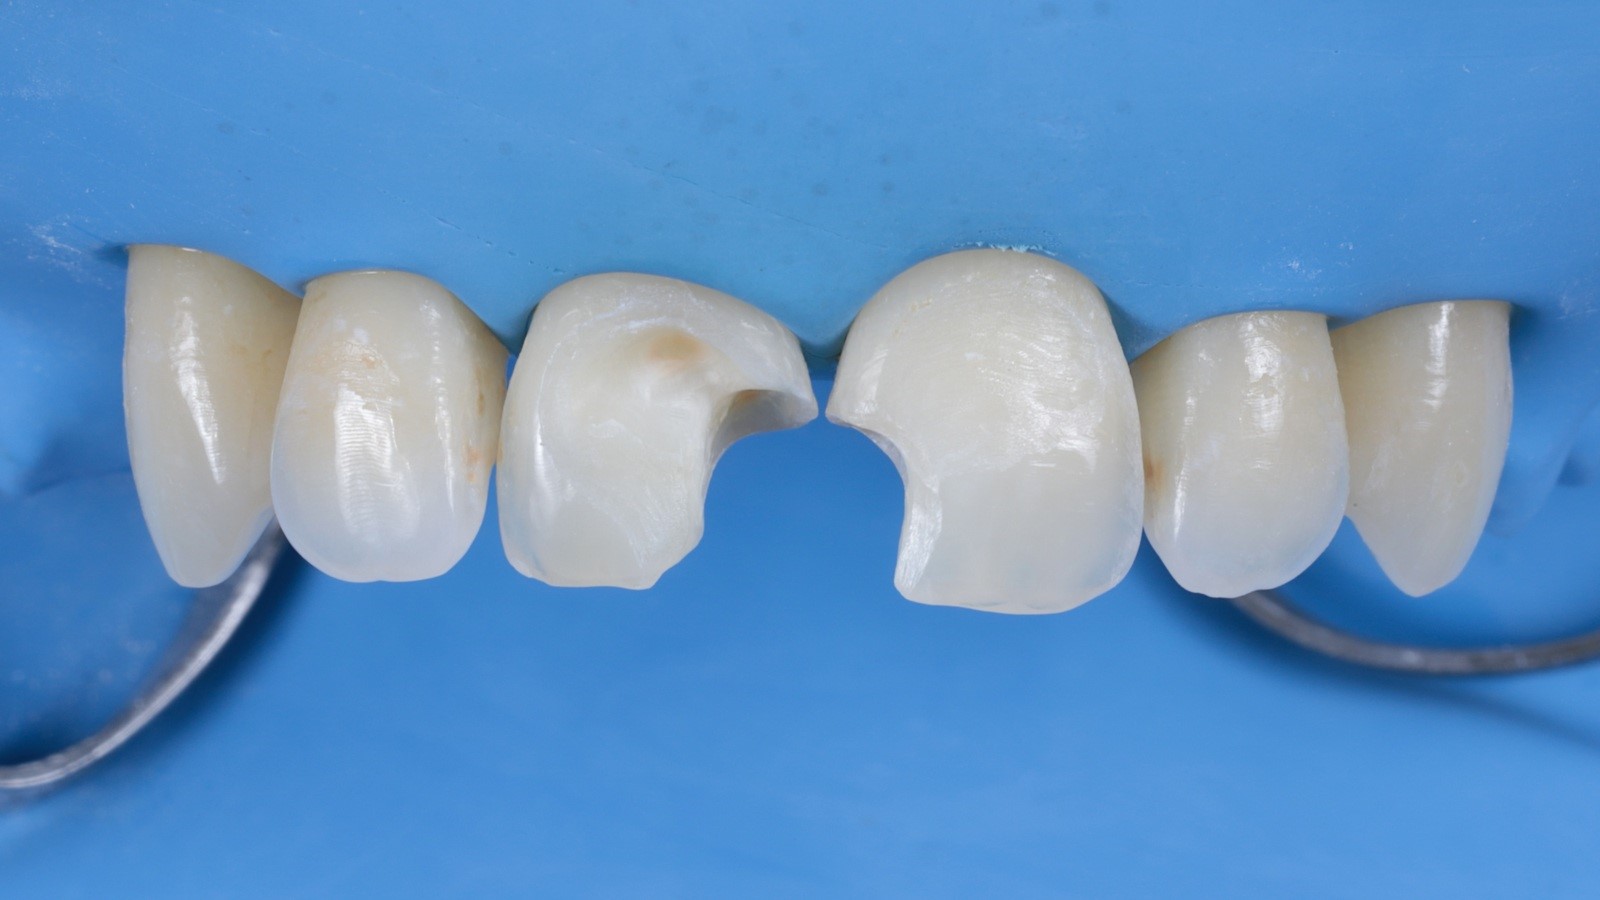

Venus Pearl MEDIUM was used to reconstruct the teeth in a single-shade layering technique. This approach can speed up the restorative procedure and significantly shorten the treatment time.

After reconstruction of the teeth with composite the restorations were ready for finishing to refine the shape.